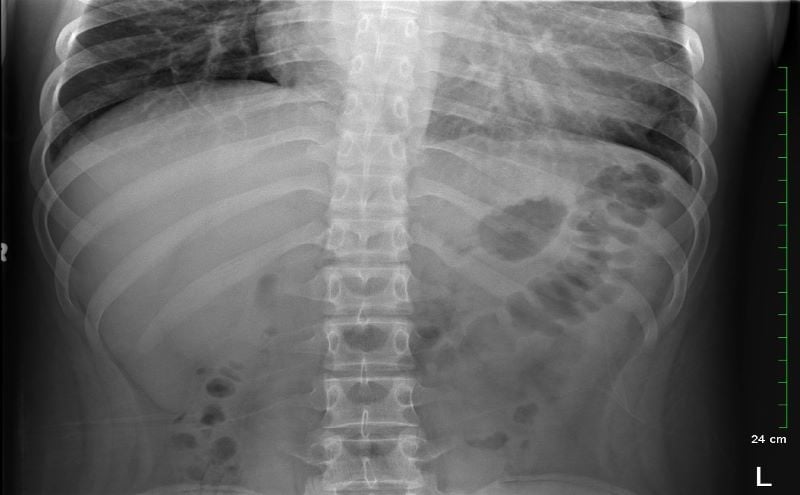

Because the patient presented with prolonged vomiting, a complete blood count (CBC), comprehensive metabolic panel (CMP), lipase, and kidney, ureter and bladder (KUB) was obtained. Initial labs showed only mild transaminitis and metabolic acidosis (AST 106, ALT 188, HCO3 15). KUB revealed the following images:

KUB read as normal by radiology. However, because of the enlarged heart border found incidentally on KUB, troponin I (0.05 ng/mL), B-type natriuretic peptide (BNP) (2186 pg/mL), and chest x-ray (CXR) was obtained, which showed the following:

With cardiomegaly confirmed, it was determined that the patient was in heart failure, and that his symptoms of abdominal pain and vomiting were likely the result of abdominal insufficiency. Cardiology performed an echocardiogram, which showed dilated cardiomyopathy, severely reduced systolic function, and a left ventricular ejection fraction of 10-15%. The patient was transferred to a cardiac surgical center for heart transplant.